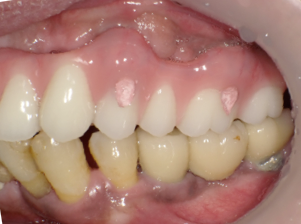

術後2週間 傷もきれいに治ってきています

術後の写真です。フレアーアウトした分、歯を引っ込めてかみ合わせも若干高くしています。

術前の口元と別人になっているのが分かると思います。

オールオンフォーの良いところはこのように好きなように歯を並べることができることです。